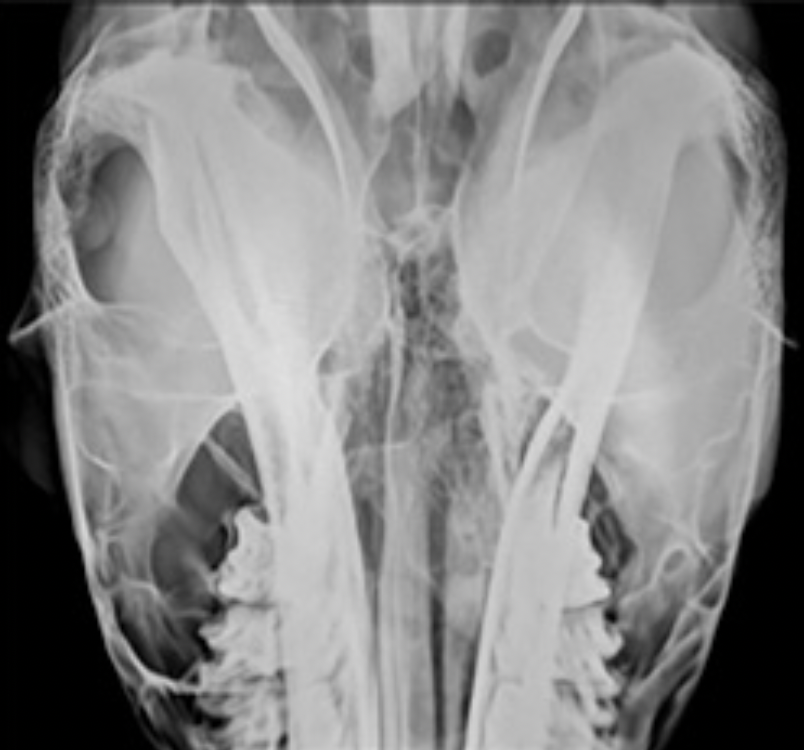

left-right oblique view equine skull

red: right mandible

orange: left zygomatic arch

grey: hyoid bones

yellow: left mandible and teeth

green: left frontal sinus

blue: left maxilla and teeth